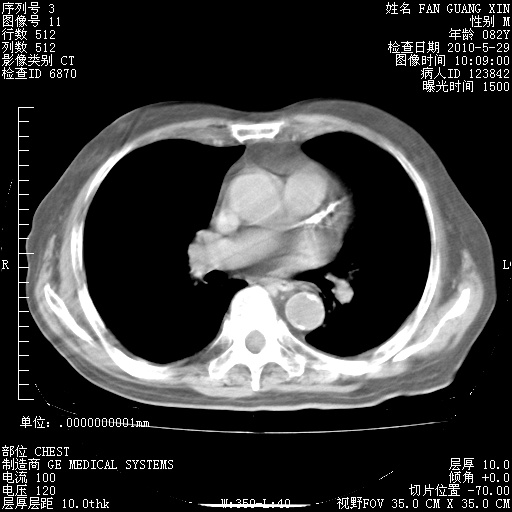

再治疗10天后的肺部CT 纵膈窗

阅读此次胸部CT,肺间质渗出性改变较入院时有吸收。目前从体温、白细胞、中性分叶明显增高,肯定存在细菌感染(发生医院感染哦,若无消化道及泌尿系统等感染的依据,肺部感染可能大)。若你院头孢哌酮舒巴坦钠耐药率较高,同意你的方案,若48小时体温仍高,可考虑使用碳青霉稀类抗菌药物,同时可予超声雾化、注意滴数时加大液体量。白蛋白33.30g/L较低哦,需加强营养等支持治疗。